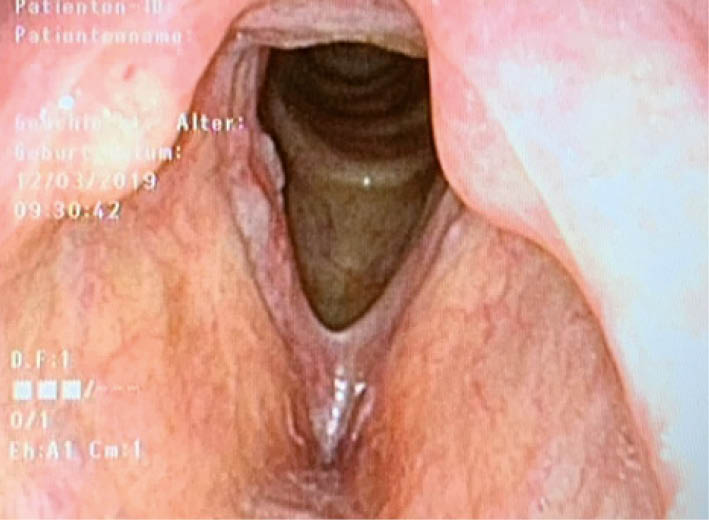

Chronische Laryngitis (Abb. 1):

Bei chronischem Nikotinkonsum (als weitere ätiologische Faktoren werden auch ein gastro-ösophagealer Reflux, Allergien, Irritation durch trockene staubige Luft oder ätzende Dämpfe, Mundatmung oder fehlende Stimmschonung nach akuter Laryngitis diskutiert).

Bei unserer Patientin zeigte sich folgender laryngostroboskopischer Befund:

Bei dieser glasigen und glatten Schwellung der beiden Stimmlippen kann eindeutig die Diagnose eines Reinke-Ödems gestellt werden. Typische Patienten sind rauchende und kommunikative Frauen im Alter von 50-60 Jahren. Eine maligne Entartung muss nicht befürchtet werden. Für die Prognose ist das Sistieren des Nikotinkonsums wichtig. Bei geringem Leidensdruck oder Initialstadium kann mit logopädischer Stimmtherapie und Nikotinstopp eine gewisse Besserung erreicht werden, in den meisten Fällen ist jedoch eine phonochirurgische Abtragung in einer kurzen Narkose nötig. Insbesondere ist eine Abtragung indiziert, wenn es bei grossen Ödemen bereits zur Belastungsdyspnoe kommt.